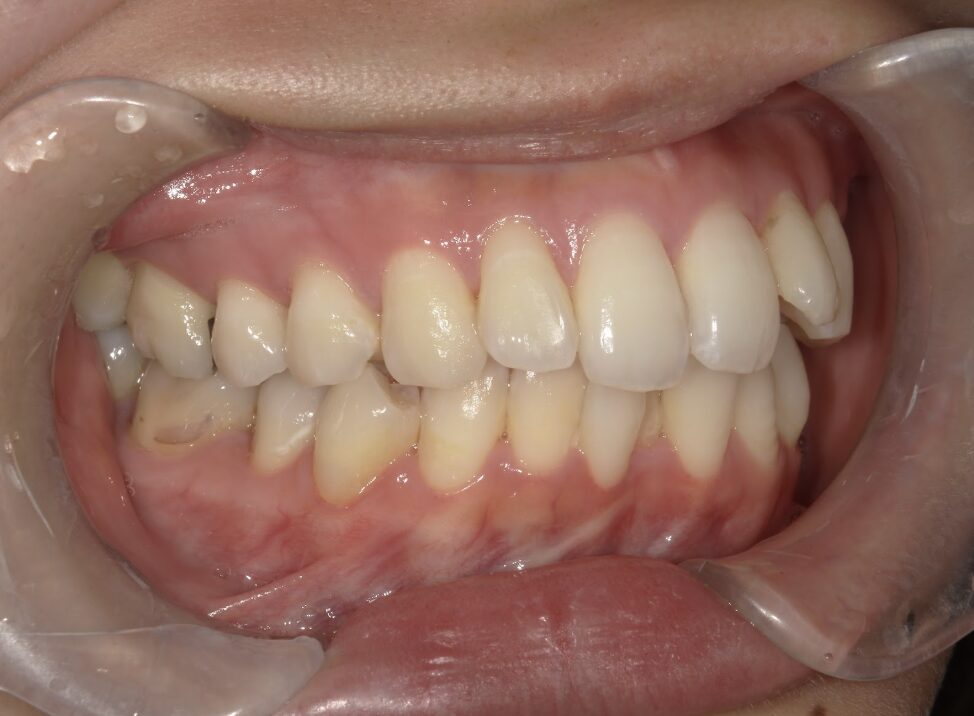

治療後

前歯が全く当たっていないを主訴に当院を受診され、開咬・上顎前突・下顎叢生を認めました。

上顎左右4番抜歯を行いIPRを使用してマウスピース型矯正装置(インビザライン)を使用し、改善を行いました。

治療期間1年9ヶ月